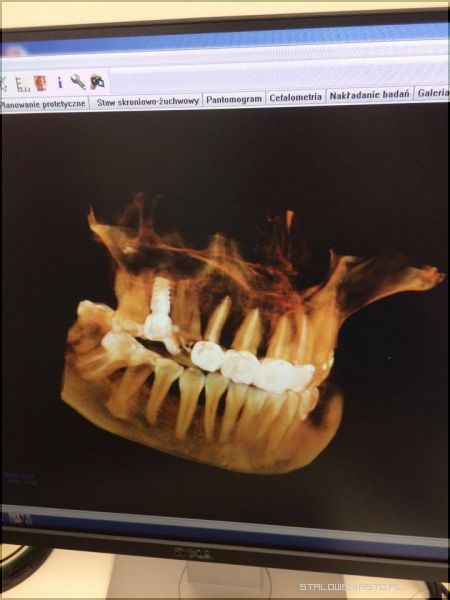

Świat zaczyna się w Stalowej WoliStomatolog Piotr Trafidło znany jest z tego, że w swojej pracy posługuje się urządzeniami i materiałami z najwyższej półki. Nie dziwi więc fakt, że w Centrum Precyzyjnej Stomatologii Multident pojawił się właśnie supernowoczesny sprzęt, na którym pracują stomatolodzy tylko w najlepszych klinikach Europy. Tego typu urządzenia w Polsce wciąż należą do rzadkości. Mowa tu o nowoczesnym tomografie umożliwiającym pozyskiwanie obrazów z rekonstrukcją 3D do aktualnie wykonywanych zabiegów. Aparat Gendex pozwala również na zmianę dawki promieniowania RTG, poprzez wykonywanie radiogramów dostosowanych do rozmiarów ciała. Jest więc bardzo bezpieczny dla pacjenta. Wykonuje zdjęcia najwyższej jakości. Dzięki niemu można precyzyjnie i szybko określić przyczynę dolegliwości, obejrzeć zęba w każdej płaszczyźnie, wykonać symulację komputerową i dotrzeć do źródła problemu bez eksperymentowania i przewidywania. Leczenie wówczas staje się tak precyzyjne, że nie ma tu możliwości popełnienia błędu przy stawianej diagnozie, a takie błędy mogą się zdarzyć, gdy korzysta się ze zwykłego aparatu RTG. Tomograf wyposażony jest również w cefalometrię co umożliwia bardzo dokładną diagnostykę wad ortodontycznych oraz zaplanowanie najlepszego leczenia ortodontycznego.

Bo diagnostyka jest najważniejszaW XXI wieku nie jest sztuką skorzystanie z pomocy stomatologa. Sztuką jest wybranie takiego gabinetu, gdzie nasze problemy zostaną rozwiązane kompleksowo, bezpiecznie, a przede wszystkim niezwykle dokładnie. Piotr Trafidło od wielu lat pracuje jako implantolog. W swojej karierze zawodowej ma na koncie blisko 2 tysiące udanych zabiegów implantologicznych. Jest „autorem” wielu uśmiechów na Podkarpaciu. Tomograf 3D pomoże mu w jeszcze lepszej diagnostyce, dzięki czemu możliwe będzie np. określenie grubości i gęstości kości, a co za tym idzie, dobranie najlepszego dla danego pacjenta implantu. Pojawienie się takiego urządzenia w Multident to rewolucja na rynku medycznym w regionie. Skuteczność leczenia będzie teraz tak duża, że firma może w ciemno zagwarantować, że w sytuacji gdyby implant jakimś cudem się nie przyjął, pacjent będzie mógł otrzymać stuprocentowy zwrot kosztów leczenia.